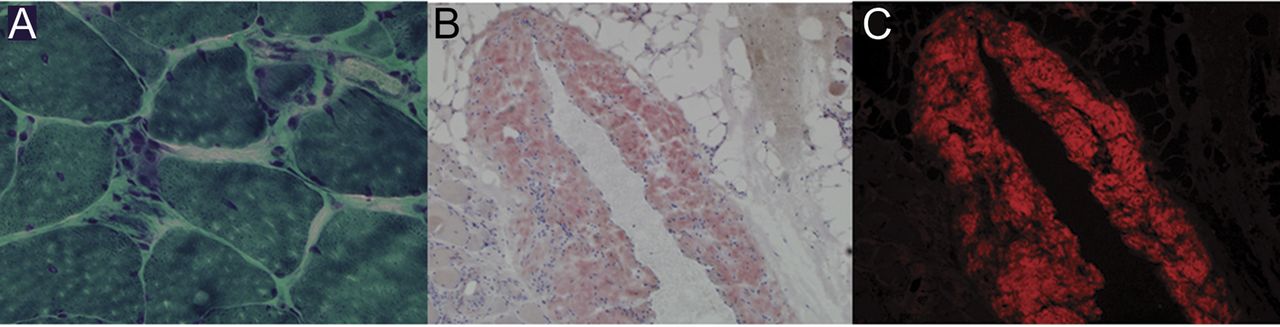

这篇文章有一个修正。请参阅:

一个69岁的人呼吸困难之后,慢慢地进步端腿无力2年以上。他巨舌(图1)。肌酸激酶是1378 U / L。三角肌活检显示肌病、去神经萎缩和congophilic存款perimysial周围血管,表明淀粉样蛋白(图2)。进一步检查发现血清单克隆λ蛋白质,骨髓淀粉样蛋白和心肌病。淀粉体肌病,underrecognized实体,主要提出了进步的近端无力在原发性淀粉样变。1呼吸困难的结果心肌病或呼吸道肌肉无力(我们的病人都)。巨舌由于淀粉样蛋白沉积是一个有用的临床线索。病人与环磷酰胺化疗、地塞米松、淀粉样变和bortezomib,改善预后。2